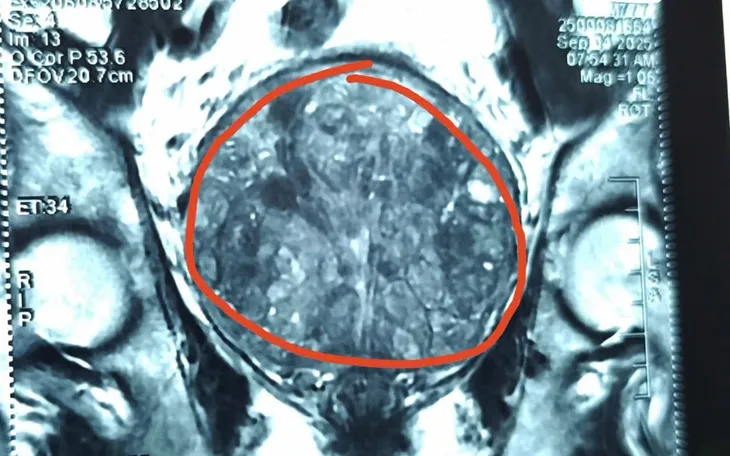

Theo bác sĩ Trần Thượng Việt, Trưởng khoa Ngoại Tổng hợp, Tiết niệu và Nam học, bệnh nhân đã được chỉ định mổ từ lâu nhưng liên tục từ chối, chỉ chọn giải pháp đặt ống thông tiểu để giảm triệu chứng. Sau ca mổ cắt trĩ, ống thông tiểu đã gây chảy máu tại tuyến tiền liệt vốn phì đại nghiêm trọng, nặng tới 484g - gấp hơn 20 lần kích thước bình thường (20-30g) và gấp 6 lần mức phì đại nặng thường gặp ở người trên 60 tuổi.

Do khối u chiếm toàn bộ vùng tiểu khung, ca phẫu thuật gặp nhiều khó khăn vì phạm vi thao tác hẹp, diện bóc tách rộng, nguy cơ chảy máu cao. Tuy nhiên, nhờ nỗ lực của ekip, ca mổ đã thành công. Sau 5 ngày, bệnh nhân hồi phục tốt, sức khỏe ổn định và chuẩn bị xuất viện.